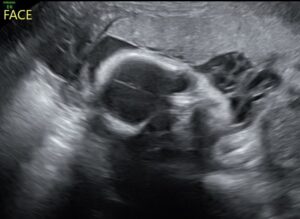

This ultrasound was done at 29 weeks, but currently 32 weeks on Friday. Only 8 more weeks till we meet our little girl and we can’t wait.